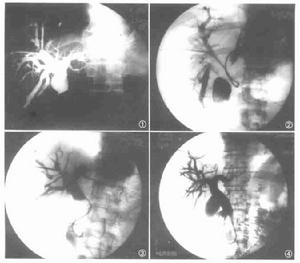

膽管擴張症--造影

膽管擴張症--造影病變部的囊狀擴張和遠端膽管的相對狹窄所引起的膽汁引流不暢甚或阻塞是導致併發症的根源。主要併發症有復發性上行性膽管炎、膽汁性肝硬變、膽管穿孔或破裂、復發性胰腺炎、結石形成和管壁癌變等。

(三)經皮肝穿刺膽道造影(PTC)在肝膽管擴張病例易於成功,可清晰地顯示肝內膽管及其流向,明確有無膽管擴張和擴張的範圍。套用於黃疸病例可鑑別其原因或梗阻部位,並可觀察到膽管壁和其內部的病理改變,依其影象的特徵以鑑別阻塞的原因。

(四)經內窺鏡逆行胰膽管造影(ERCP)藉助於十二指腸鏡可經乳頭開口插管將造影劑直接注入膽管和胰管內,查明膽管擴張的範圍和梗阻部位, 並能顯示胰膽管共同通道的長度和異常情況。

(六)術中膽道造影在手術時將造影劑直接注入膽總管內,可顯示肝內、外膽管系統和胰管的全部影像,了解肝內膽管擴張的範圍、胰管膽管的返流情況, 有助於選擇術式和術後處理。